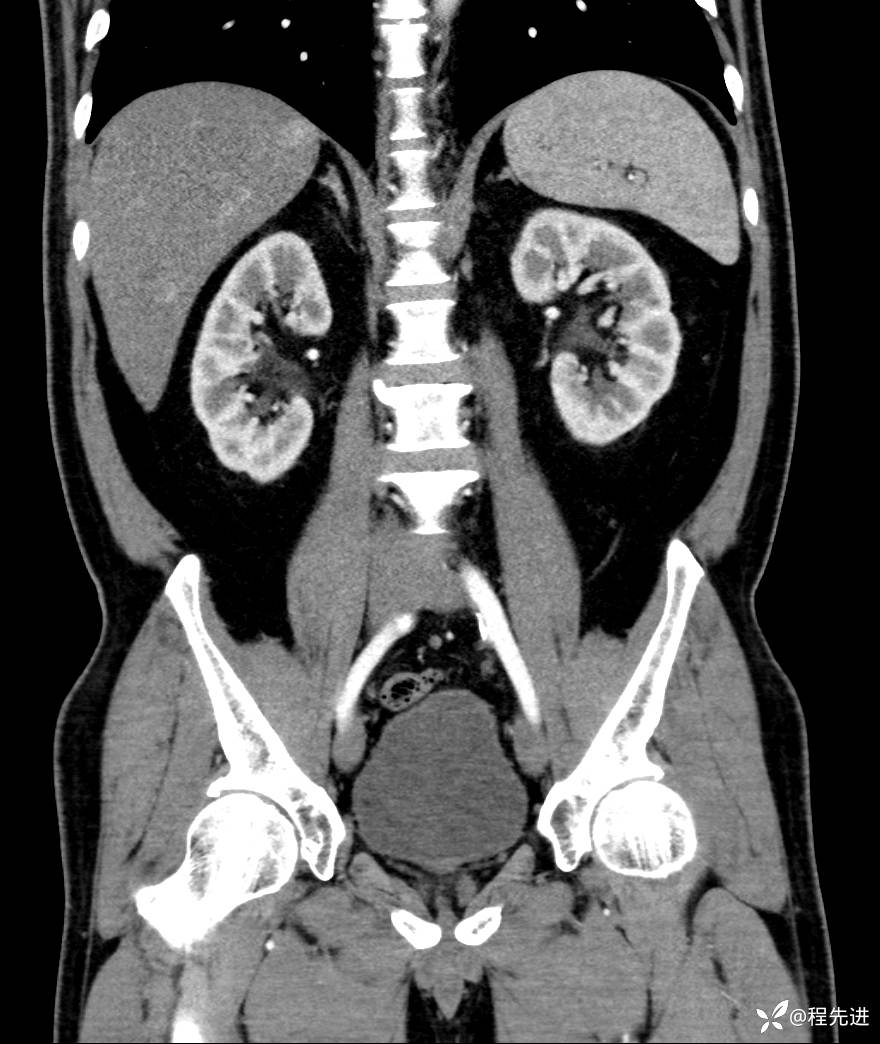

【腹盆】特别精彩病例|发现腹膜后肿物1月余

主诉:发现腹膜后肿物1月余

现病史:患者1月余前查体,行超声检查提示:后腹膜囊实性肿块;慢性胆囊炎伴胆囊内结石;无腹痛腹胀,不伴腹泻发热等;偶感腰背部酸痛。

CT平扫+增强: